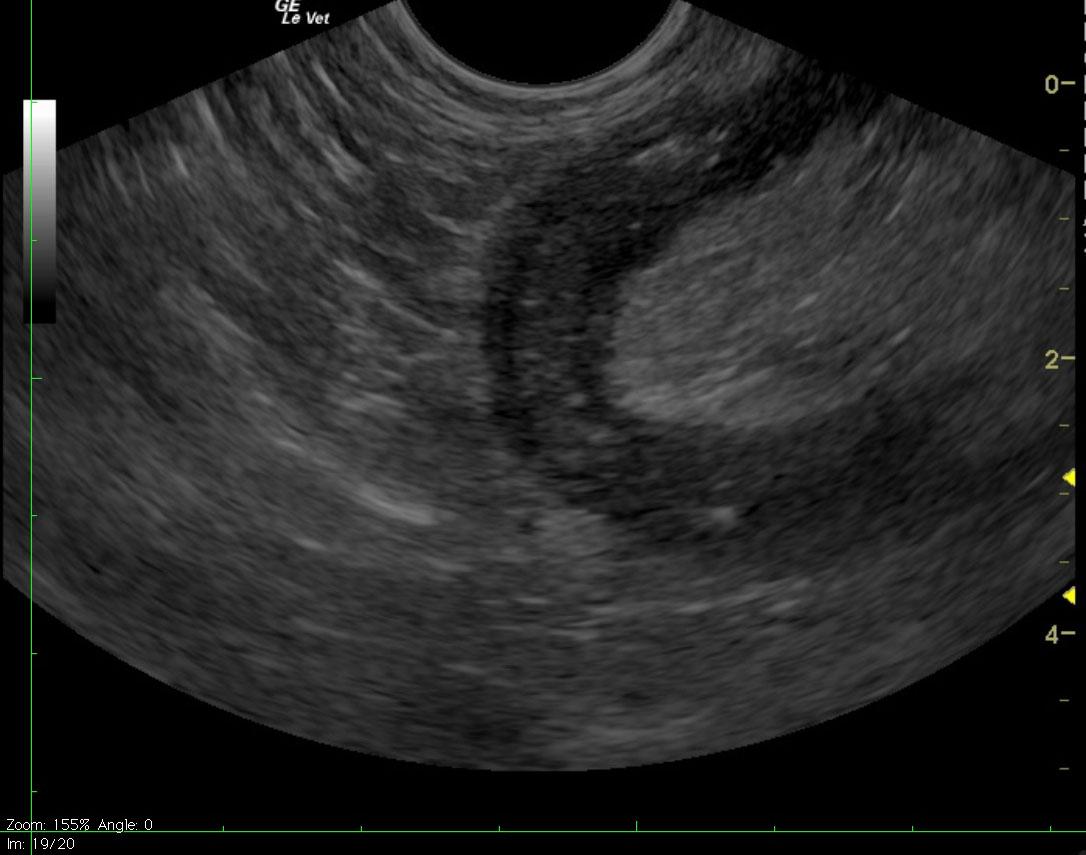

Ultrasound reveals marked gastric distention with fluid, dependent echogenic contents and a small amount of gas. Complete loss of gastric peristalsis appears to be present. Mild-to-moderate fluid distention of the proximal small intestines is also apparent. The proximal small bowel walls are thickened and hypoechoic with subtle loss of distinction between layers. The affected small intestines appear to be bordered by mildly echogenic mesenteric fat.